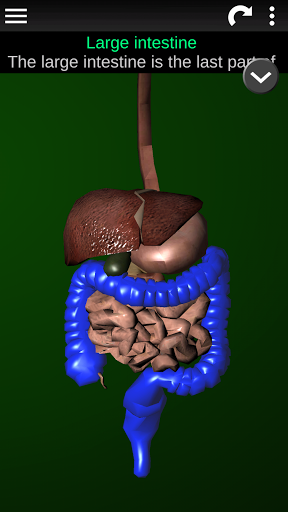

Internal Organs in 3D Anatomy لـ Vodafone Smart N9 Lite

(الأجهزة الداخلية في)

Organs 3D Anatomy 2.0.12

يمكنك هنا تنزيل ملف حزمة تطبيق أندرويد "Internal Organs 3D Anatomy" الخاصة بجهازVodafone Smart N9 Lite مجانًا، نسخة ملف حزمة تطبيق أندرويد - 3.4 للتحميل على Vodafone Smart N9 Lite اضغط ببساطة على هذا الزر. إنه سهل وآمن. نحن نقدم فقط ملفات حزمة تطبيق أندرويد الأصلية. إذا انتهكت أية مواد موجودة في الموقع حقوقك قم بإبلاغنا من خلال